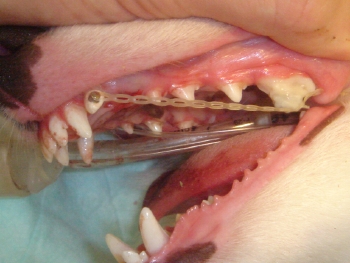

移動中の写真です。

下顎の犬歯が上顎の切歯と犬歯の間に入るようにカバーをします。

前述の写真のコメントです。下顎犬歯カバーにより犬歯を適正な位置に移動させます。